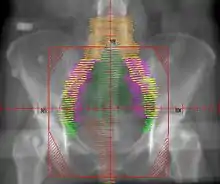

المعالجة الإشعاعية

يُستخدم العلاج الإشعاعي المساند بصورة شائعة في حالات سرطان بطانة الرحم ذات المرحلة المبكرة (المرحلة الأولى أو الثانية)، يُمكن أن يتم إيصاله عن طريق المعالجة الكثبية المهبلية -التي تُصبح الوسيلة المفضلة نتيجة لنقص سُمِّيّتها- أو عن طريق العلاج الإشعاعي بحزمة شعاعية خارجية، تشمل المعالجة الكثبية وضع مصدر الإشعاع في العضو المُصاب، ففي حالة سرطان بطانة الرحم يتم وضع مصدر الإشعاع مُباشرةً في المهبل، يشمل العلاج الإشعاعي ذو الحزمة الخارجية حزمة من الإشعاعات تصوَّب إلى المنطقة المصابة من خارج الجسم، وتستخدم المعالجة الكثبية المهبلية لعلاج أي سرطان أخمص متبقي في المهبل، بينما يُمكن أن يُستخدم العلاج الإشعاعي ذو الحزمة الشعاعية الخارجية لعلاج السرطان المتبقي في الحوض بعد الجراحة، ومع ذلك فإن فوائد العلاج الإشعاعي المساند مثيرة للجدل، حيث يقل معدل الانتكاسة في الحوض مع استخدام العلاج الإشعاعي بحزمة خارجية بصورة ملحوظة، لكن لا يتحسن معدل الانبثاثات ومعدل البقاء على قيد الحياة[4]، توفر المعالجة الكثبية المهبلية جودة أفضل للحياة من العلاج الإشعاعي بحزمة خارجية.[21]

يُمكن أن يُستخدم العلاج الإشعاعي أيضًا قبل الجراحة في حالات معينة، فعندما تُظهر صور ما قبل العملية أو التقييم السريري غزو الورم لعنق الرحم يمكن أن يتم إجراء الإشعاع قبل القيام باستئصال الرحم كاملًا[13]، يمكن أن يتم استخدام أيضًا المعالجة الكثبية أو بحزمة خارجية –كلٌ على حدة أو الاثنين معًا- عندما يكون هناك موانع لإجراء استئصال الرحم[21]، وكلتا الوسيلتين للعلاج الإشعاعي يكون لها آثار جانبية تصيب خاصةً القناة الهضمية.[4]